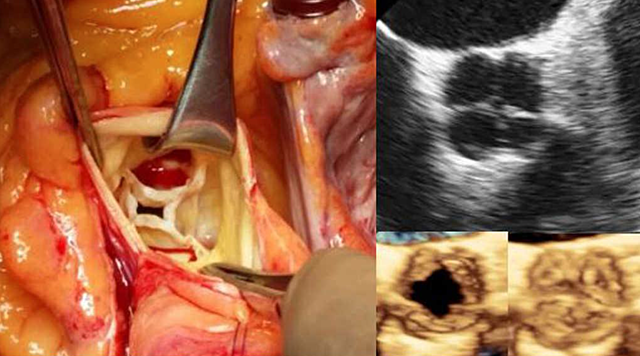

La válvula cardíaca protésica implantable percutánea se ha convertido en un área importante. En Ruen Francia y gracias al Dr. Cribier. Se desarrolló una válvula cardíaca implantada percutáneamente compuesta por 3 valvas pericárdicas bovinas montadas dentro de un stent expansible con balón. La primera implantación se realizó en varón de 57 años con estenosis aórtica calcificada, shock cardiogénico, isquemia subaguda de la pierna y otras enfermedades no cardíacas asociadas.